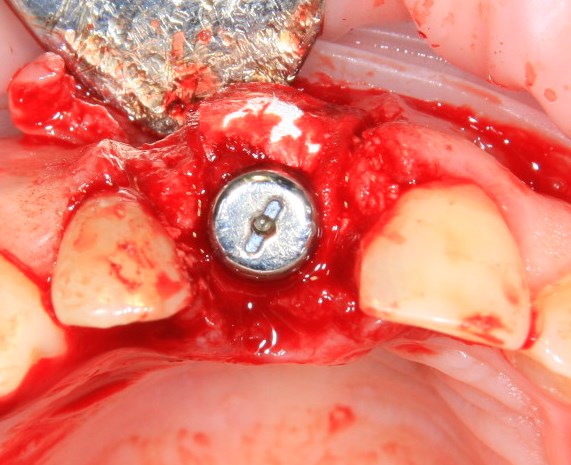

Немедленная имплантация — оптимальное решение в любой клинической ситуации